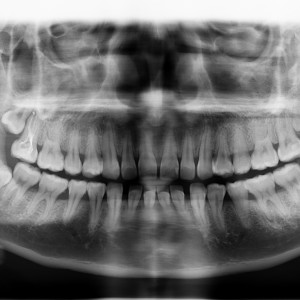

術(shù)前